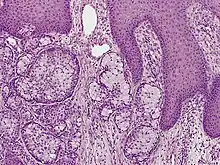

| Eccrine carcinoma, alveolar type | |

Eccrine carcinoma is a rare skin condition characterized by a plaque or nodule on the scalp, trunk, or extremities.[1]: 669 It originates from the eccrine sweat glands of the skin, accounting for less than 0.01% of diagnosed cutaneous malignancies.[2] Eccrine carcinoma tumors are locally aggressive, with a high rate of recurrence. Lack of reliable immunohistochemical markers and similarity to other common tumors has made identification of eccrine carcinoma difficult.[2]